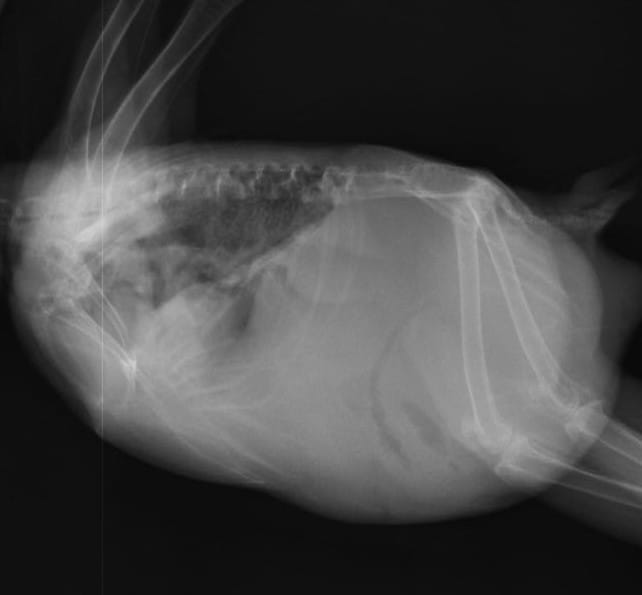

こちらはレントゲン写真ですが、かなり腹水が溜まっていました。超音波検査でも同様の所見でした。

体重も腹水分、元の体重より増えていました。